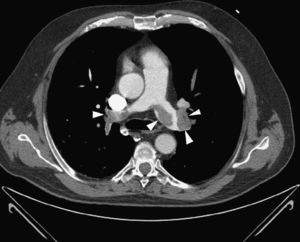

Case 2A 78-year-old woman was admitted to the emergency room with shock, respiratory failure and impaired consciousness. She had undergone colorectal surgery 15 days previously. There was no visible blood loss, although she had had severe rectal bleeding in the previous week. Given the absence of blood pressure response to fluid therapy, elevated troponin T and severe RV dilatation and functional impairment on TTE, it was decided to perform thoracic CT angiography, which revealed bilateral central PE, with subtraction images suggestive of multiple thrombi in the main right and left pulmonary arteries and all the lobar and segmental branches, causing significant luminal obstruction, particularly of the lower lobe arteries.

Given the suspicion of obstructive shock due to high-risk PE, intravenous thrombolysis was performed with a 50-mg bolus of alteplase, which resulted in spontaneous permanent return of circulation after around 45 min of ALS. Thoracic CT angiography showed thromboembolic foci in the distal portion of both pulmonary arteries, in the origin of several lobar arteries, and most noticeably in the segmental branches of the right lower lobe artery (Figure 2). As the setting of shock remained refractory to supportive measures, it was decided to perform RT using the AngioJet® system, which resulted in immediate hemodynamic improvement and partial angiographic improvement. The patient remained under ventilatory and inotropic support for 10 days, followed by a favorable clinical course and complete neurological recovery. TTE performed one month after the acute event showed no RV dilatation or dysfunction or signs of PH (Figure 3B). The patient was discharged after 37 days.